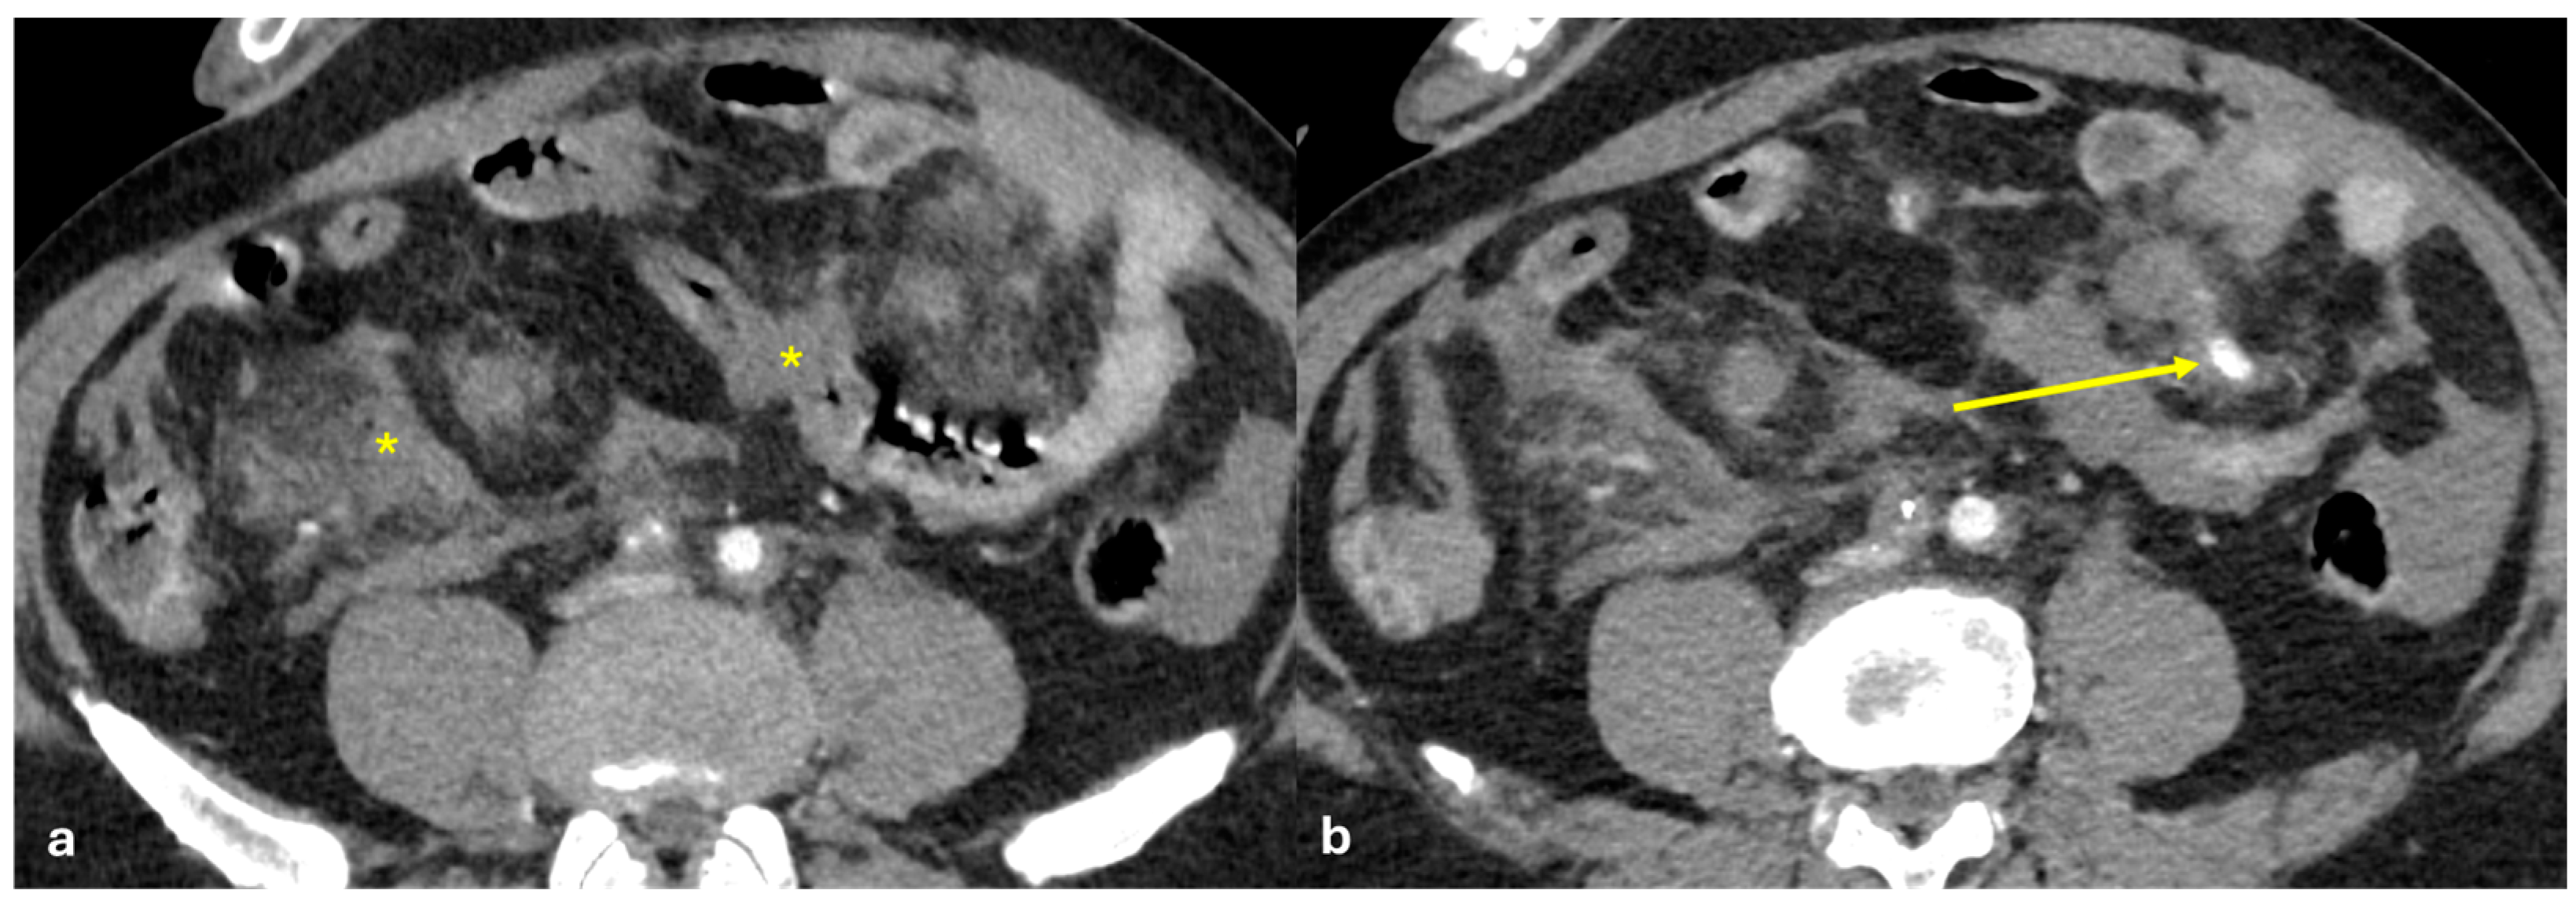

- Micro-nodular pattern: micro-nodules with a diameter ≤ 5 mm (Figure 1);

- Nodular pattern: nodules with a diameter > 5 mm (Figure 2a);

- “Omental cake”: nodular thickening of the omentum (Figure 2b);

- Plaque pattern: confluent nodular plaques, typically involving the lower surface of the right diaphragm (Figure 3);